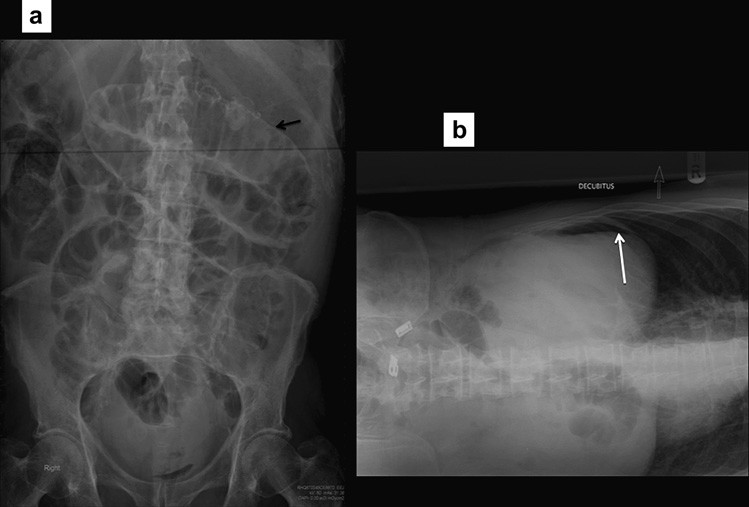

Các dấu hiệu trên phim thường quy là các quai ruột non bị giãn, đường kính trên 30 mm ở đoạn gần và trên 25 mm ở đoạn xa. Các mức khí dịch có chân rộng hơn 25mm là bất thường, các mức khí-dịch của một quai ruột ở các độ cao khác nhau (hình bậc thang) và các bóng khí bị kẹt giữa các quai ruột giãn (dấu hiệu hình tràng hạt) cũng là dấu của hiệu tắc ruột. Ít phổ biến, nếu các quai ruột bị giãn chứa đầy dịch thì phim X quang bụng cho thấy các quai ruột trong ổ bụng rất ít khí làm tăng nghi ngờ tắc ruột ở bệnh nhân có triệu chứng lâm sàng. Các dấu hiệu X quang có thể xuất hiện trước các triệu chứng lâm sàng từ 6 đến 12 giờ. Hình 1 cho thấy một vài dấu hiệu X quang của tắc ruột non.

Hình 1. Tắc ruột non. (a) Nhiều quai ruột non giãn, chứa đầy khí. Lưu ý nhiều nếp vòng theo chu vi ruột. (b) Rất ít khí do ruột non bị tắc chứa đầy dịch. (c) Phim X quang bụng chụp đứng cho thấy nhiều mức khí dịch-hình “bậc thang”.